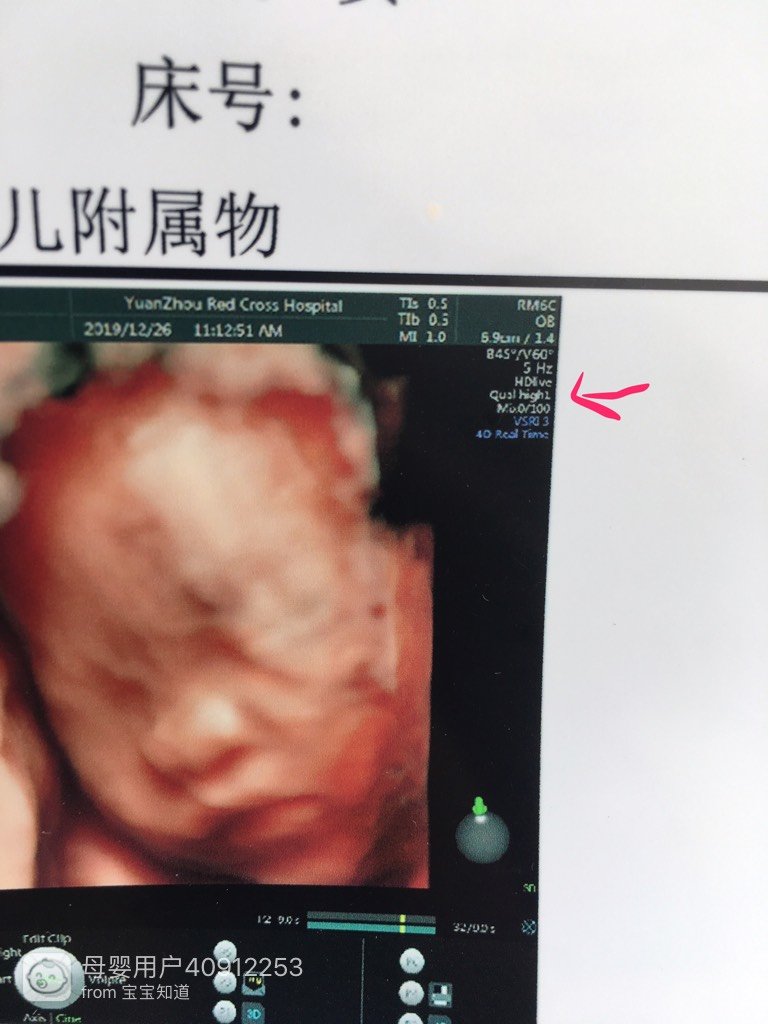

有会看府坐的宝妈吗?唤金好想知道是不堡贸告是女儿

看数据显示是女孩